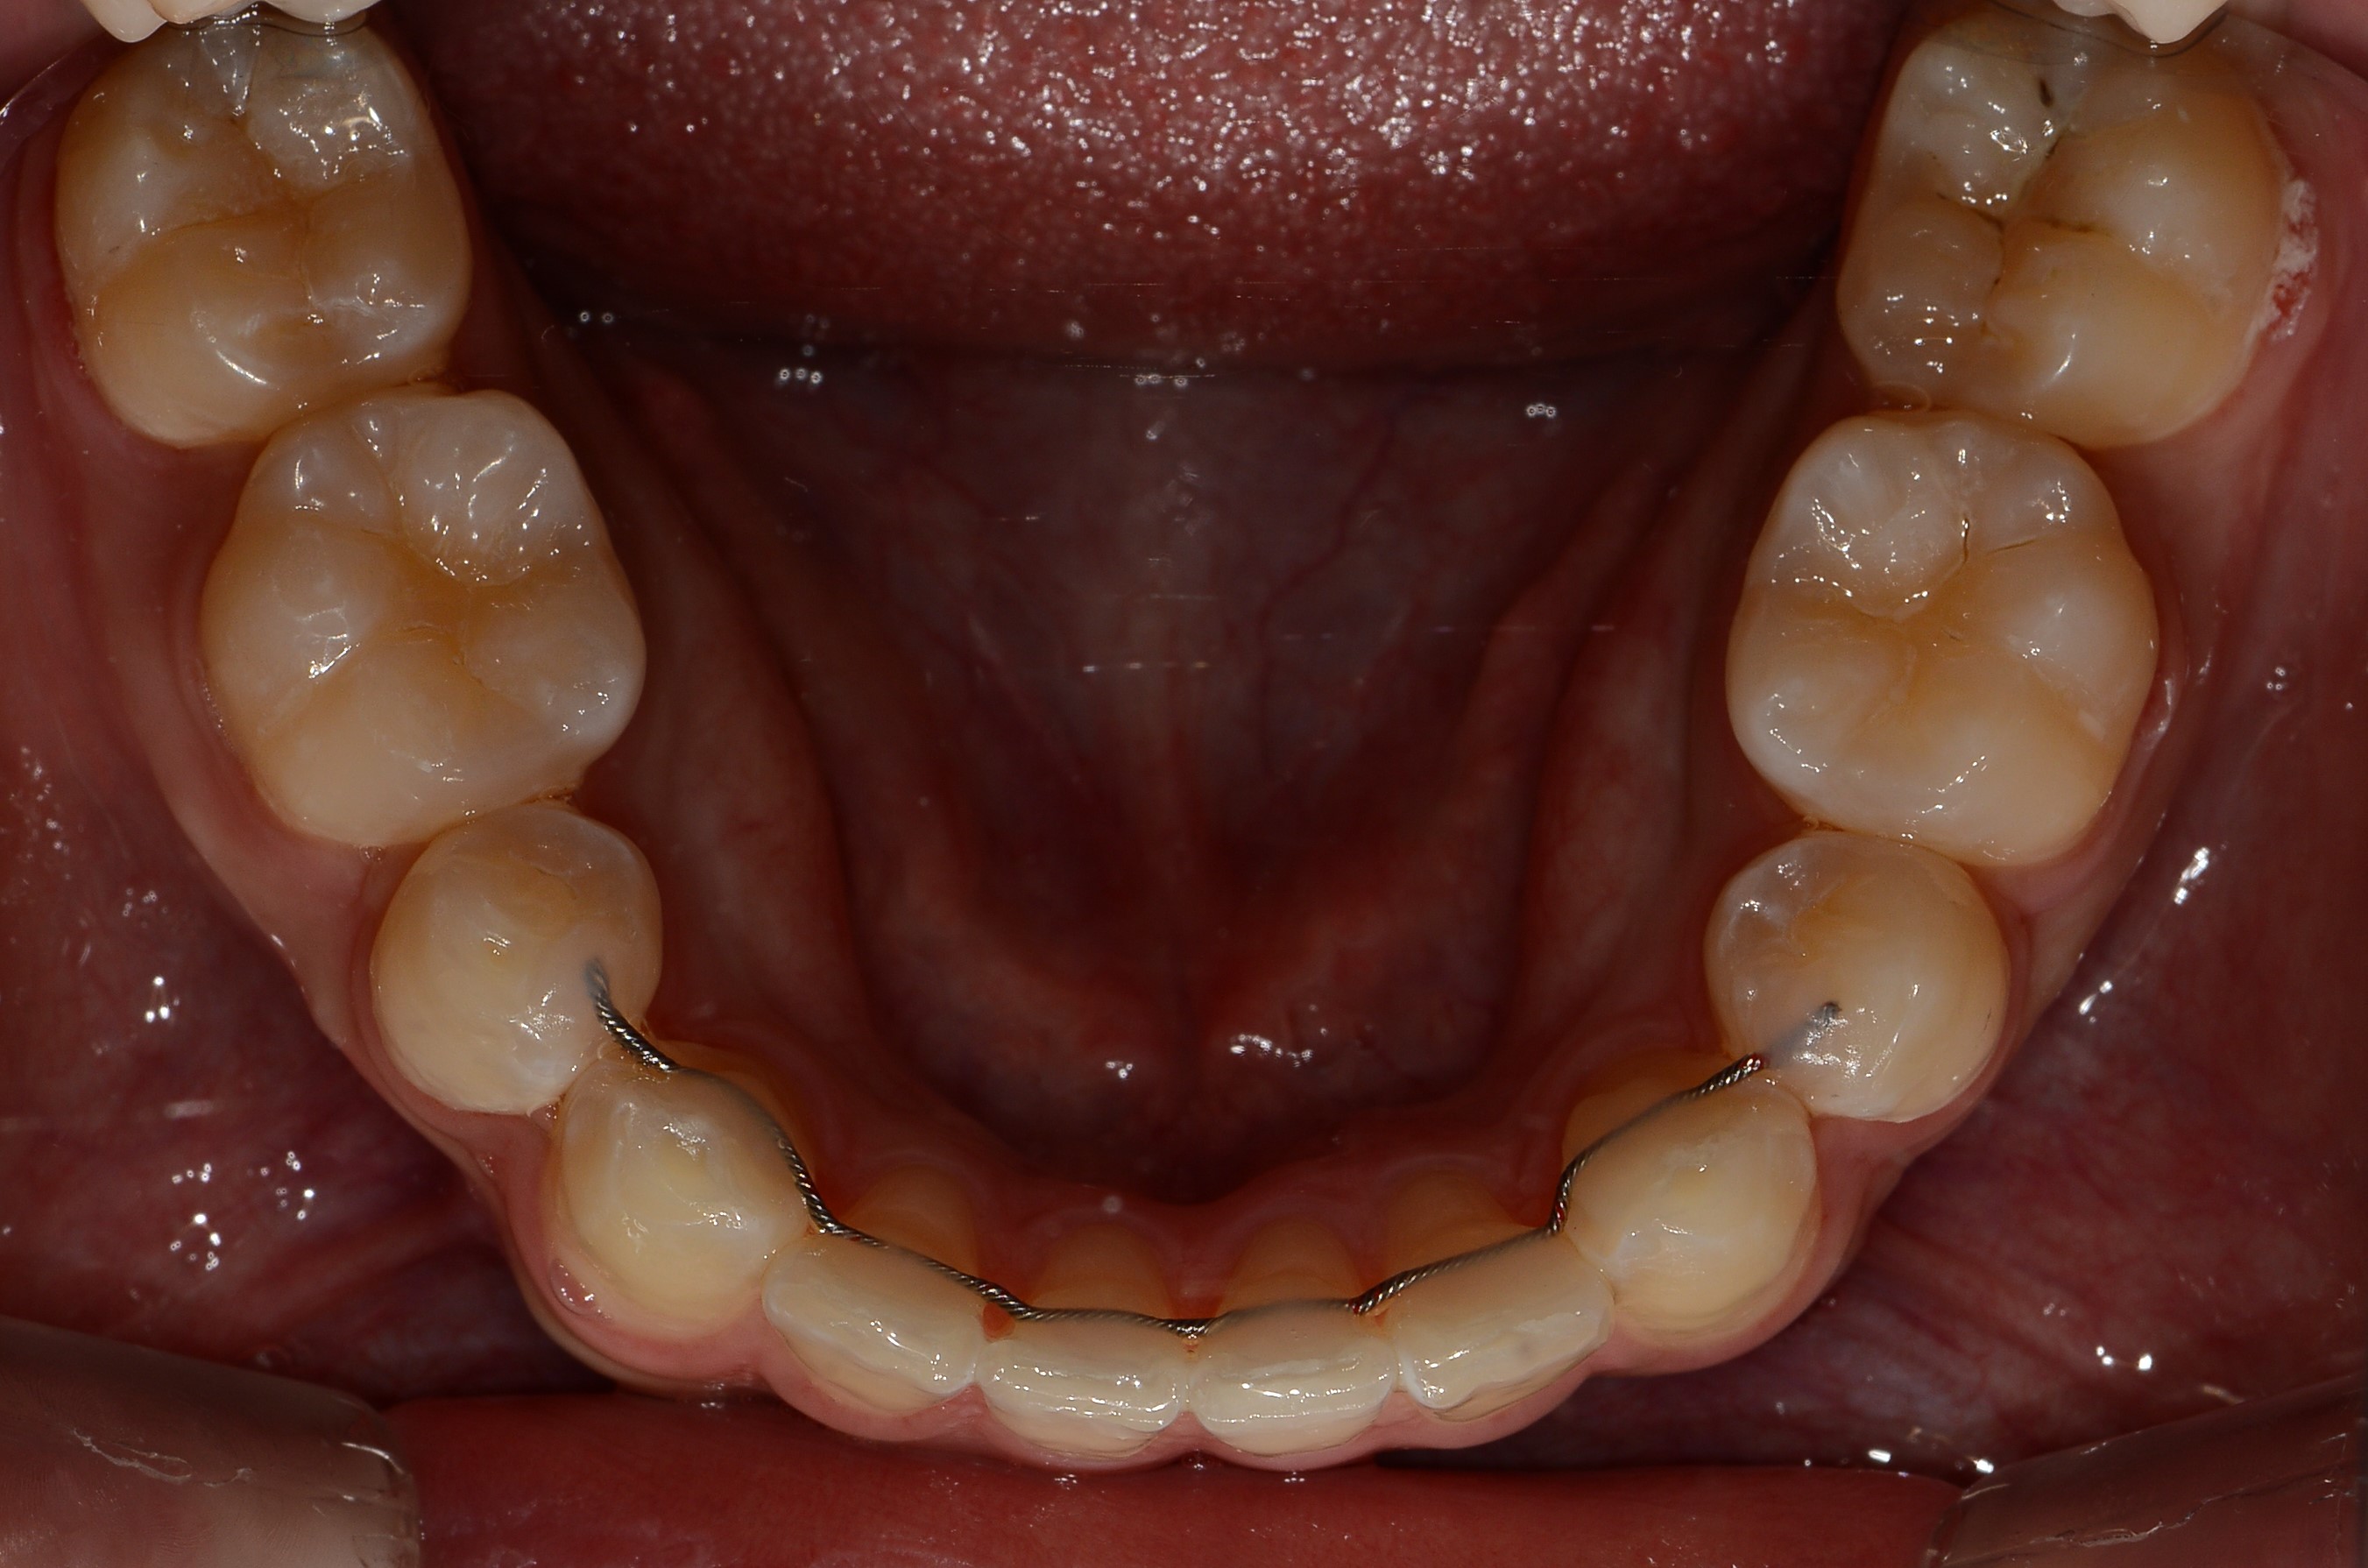

치료 전 사진입니다.